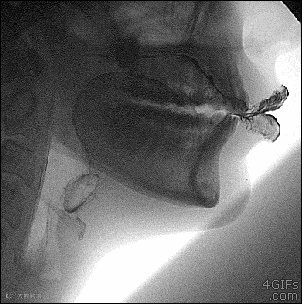

11. X光下人的口腔